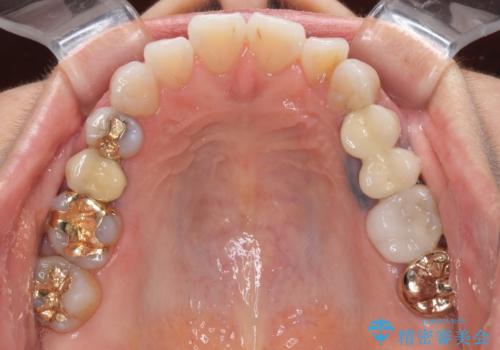

- 歯肉が退縮したためにクラウンの縁や歯根が見えてしまっていることを気にして来院された患者様です。

また、歯肉が黒く変色していることも気になるとのことでした。

仮歯に変える際に歯肉の一部を切除し、金属片による変色を除去した後、オールセラミッククラウンにて補綴することとしました。

メタルタトゥー(金属イオンの溶出による歯肉の変色)は、歯に装着された金属から金属イオンが溶け出したり、金属を除去するときの切削片が歯肉に入り込んでしまったりして引き起こされます。

物理的に除去をすることできれいな歯肉となりますが、残留している金属イオンにより再発するリスクがあります。